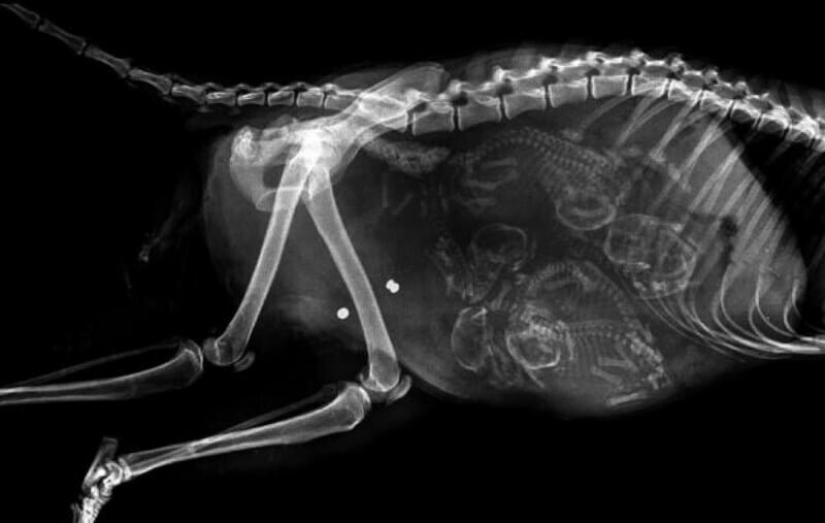

Chinchilla